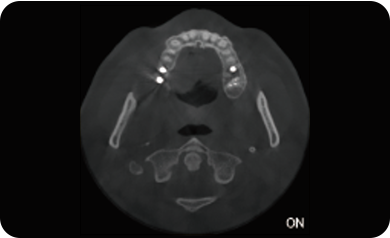

超能去伪 至臻影像

局部超清显示、 移动视野摄片

可根据临床需求任意调整成像区域大小实现局部超清三维显示

临床样片